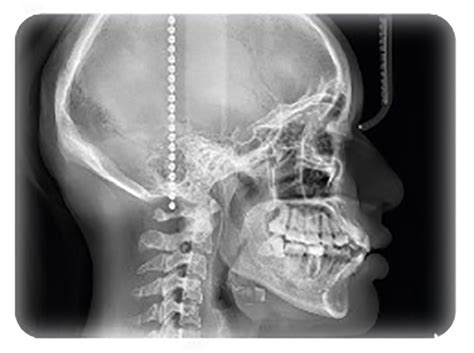

El término Cefalometría, del griego “Kephale” (cabeza) y “metron” (medida), es el conjunto de procedimientos seguidos para la medición de la cabeza, la descripción y cuantificación de las estructuras involucradas en la maloclusión (huesos, dientes y tejidos blandos).

La Cefalometría radiográfica se realiza mediante una radiografía lateral de cráneo o telerradiografía.

Figura 1. Planos cefalométricos

Radiografía Cefalométrica